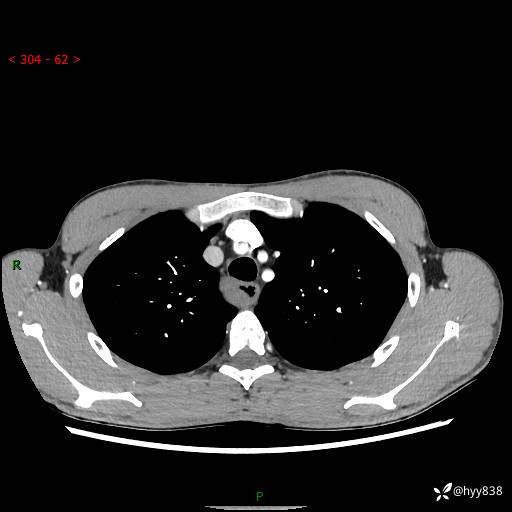

年轻男性,发现后纵隔占位1周余。征象简单,难在定位---结果公布~

现病史:患者于1周前体检行检查发现后纵隔占位,患者平素无明显咳嗽咳痰,无心慌、胸闷、胸痛、呼吸困难、低热、盗汗,无头痛、头晕,无腹痛、腹胀等不适。现患者欲求进一步治疗,遂来我院就诊,以“纵隔占位”收入我科。 患者自起病以来,精神可,睡眠可,饮食可,大小便正常,体重无明显改变。

胸部CT平扫+增强